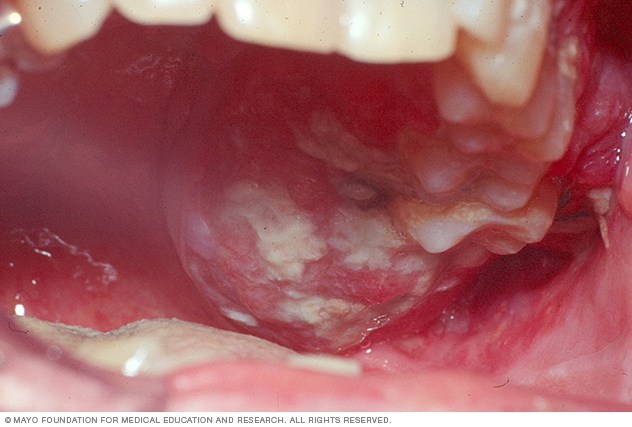

Koreya y’Epfo ni yo yonyine ishyira ikimenyetso ku nzoga kigaragaza ko zishobora gutera kanseri y’umwijima. Mu 2016, Statnews.com yashyizeho amabwiriza yerekana ingaruka zitandukanye z’inzoga, harimo kanseri y’umwijima iyo mukanwa, amabere, umuhogo n'ahandi. Ibi byerekana ko ibihugu bikeneye gukaza amabwiriza ku nzoga mu rwego rwo kurinda ubuzima bw’abaturage.

Ubushakashatsi bushya bwagaragaje ko inzoga ari mbi cyane